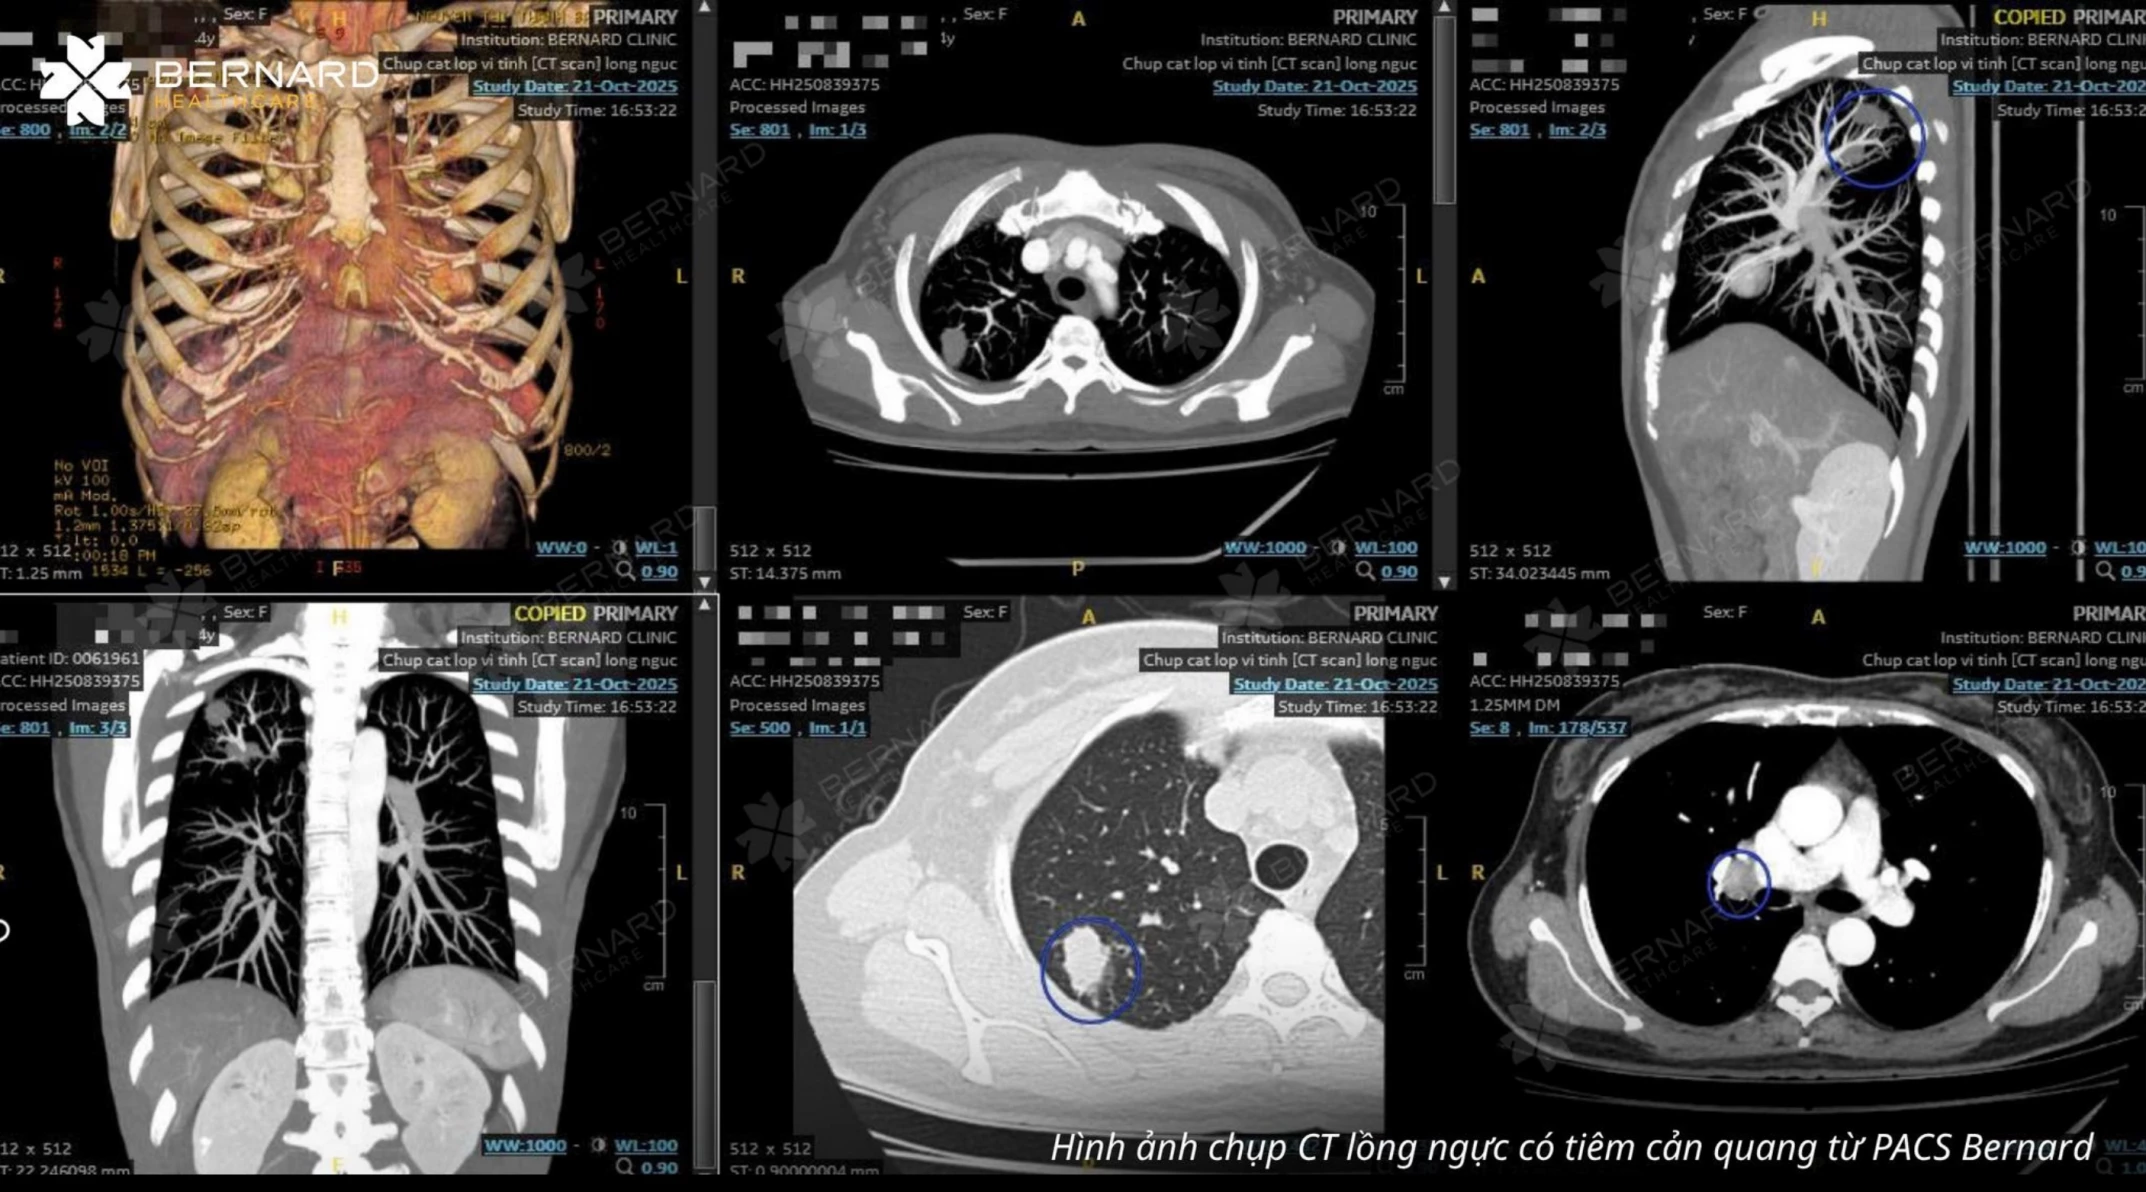

Nhằm xác định rõ bản chất tổn thương, khách hàng được chỉ định chụp CT lồng ngực có tiêm thuốc cản quang.

Kết quả CT cho thấy nhiều bất thường cần theo dõi chặt chẽ: Tổn thương choán chỗ S1-2 phổi phải kích thước 1,7 x 2, 1 cm, bờ tua gai (dấu hiệu gợi ý u ác tính), nốt khác tại S2 phải (1,3 x 1,7 cm), bờ không đều, nốt dưới màng phổi S6 phải, đường kính 4mm, hạch rốn phổi phải và hạch trung thất nhóm 2, 4 tăng kích thước, cần theo dõi di căn hạch vùng, ổ đậm độ thấp tại gan hạ phân thùy IV, khả năng liên quan tổn thương di căn xa.

TS.BS.CK2 Nguyễn Đại Hùng Linh - Phụ trách Chẩn đoán hình ảnh Bernard Healthcare kết luận gợi ý u phổi phải tại S1-2 và S2, theo dõi di căn hạch rốn phổi và trung thất, tổn thương gan nghi ngờ di căn kèm thoái hóa cột sống ngực.